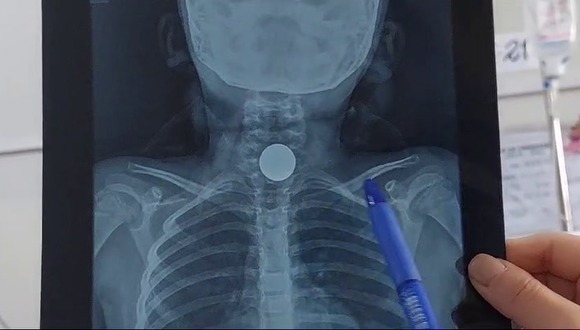

“La moneda estaba alojada en el esófago, luego de varias placas, evaluar el riesgo quirúrgico y la aplicación de anestesia, la extracción fue un éxito, el objeto pudo haber pasado por el tubo digestivo y ocasionar más problemas, tenía dolor, inflamación y náuseas. Tenía dificultad respiratoria”, citó la médico Adriana Zapata.